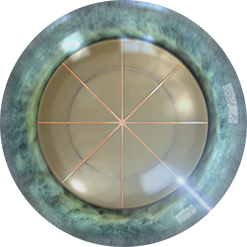

프리미엄 레이저 120º 다면 절개를 이용한

절개부위의 고정으로 충격에 강합니다.

절개 부위가 고정된

레이저 다면 절개